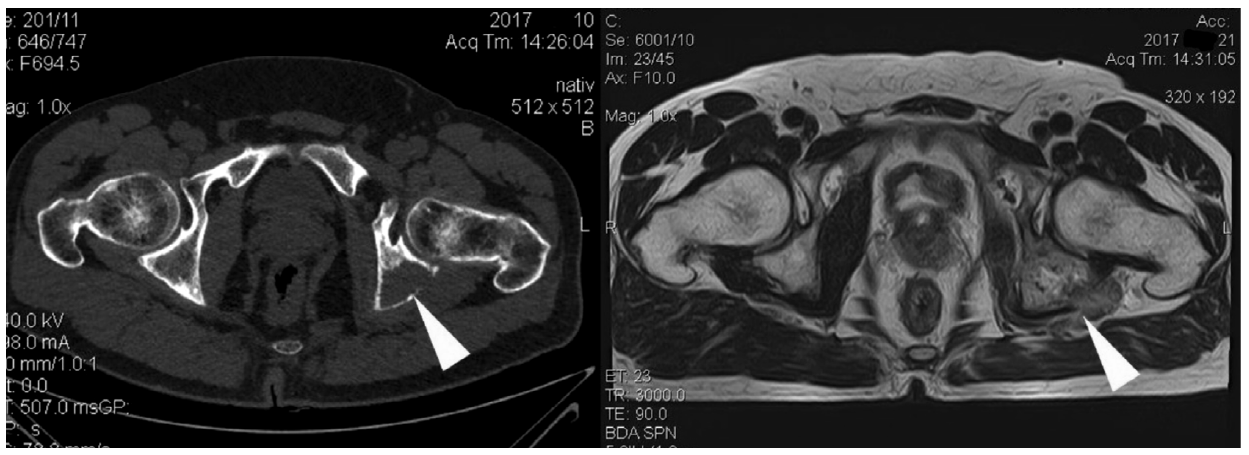

Рис. 1. КТ костей таза и магнитно-резонансная томография костей таза пациента с метастатическим поражением параацетабулярной области до проведения хирургического лечения.

Fig. 1. CT of pelvic bones and a pelvis magnetic resonance imaging scan of the patient with para-acetabular part metastases before the surgical treatment.

Рис. 2. Рентгенография костей таза в прямой проекции после выполнения параацетабулярной резекции с эндопротезированием модульным эндопротезом на основе конической ножки.

Fig. 2. X-ray of pelvic bones in direct projection after para-acetabular resection with endoprosthesis replacement using modular endoprosthesis based on conical leg.

Из 16 пациентов, которым выполнены радикальные резекции, у 11 использован реконструктивно-пластический компонент операции. В качестве пластического компонента выполнялось перемещение мышечного лоскута на сосудистой ножке для замещения дефекта тканей у 4 больных, композитные сетки использовались у 2 пациентов. Во время реализации реконструктивного этапа также применялись различные варианты металлоостеосинтеза. Одному пациенту, которому выполнялась параацетабулярная резекция с целью восстановления целостности тазового кольца и достижения хороших функциональных результатов, проведено эндопротезирование модульным эндопротезом на основе конической ножки (рис. 1, 2).